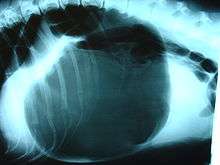

X-ray from the underside of a dog with severe intestinal gastric dilatation volvulus. The dark area is the buildup of gas. Surprisingly, this animal survived.